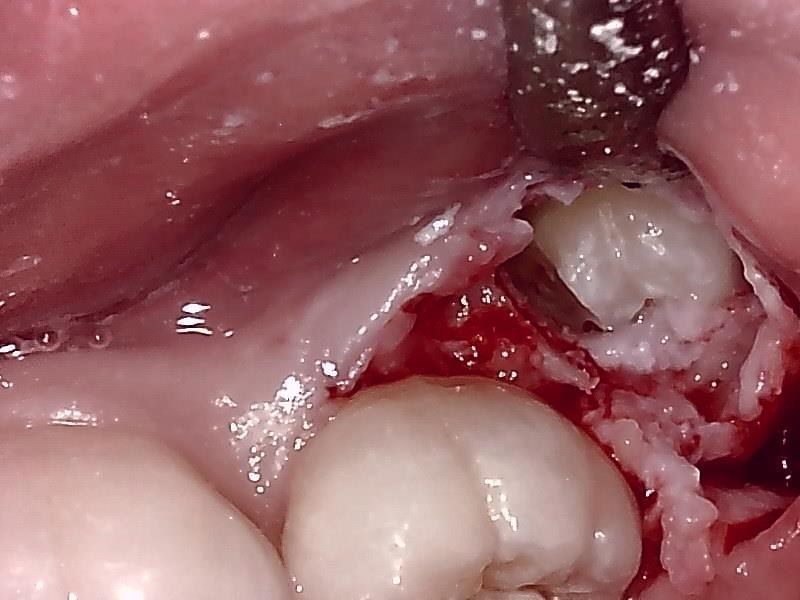

切開して歯肉剝離する。

歯冠を明示する。